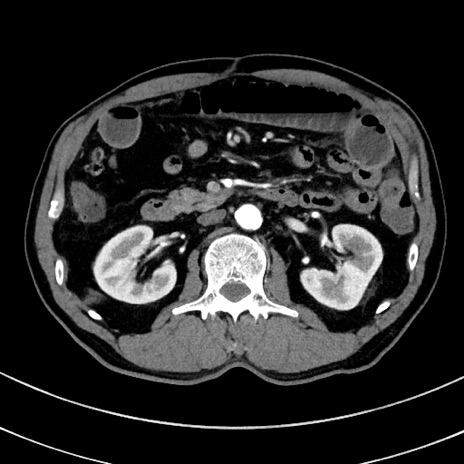

症例

冠状断像